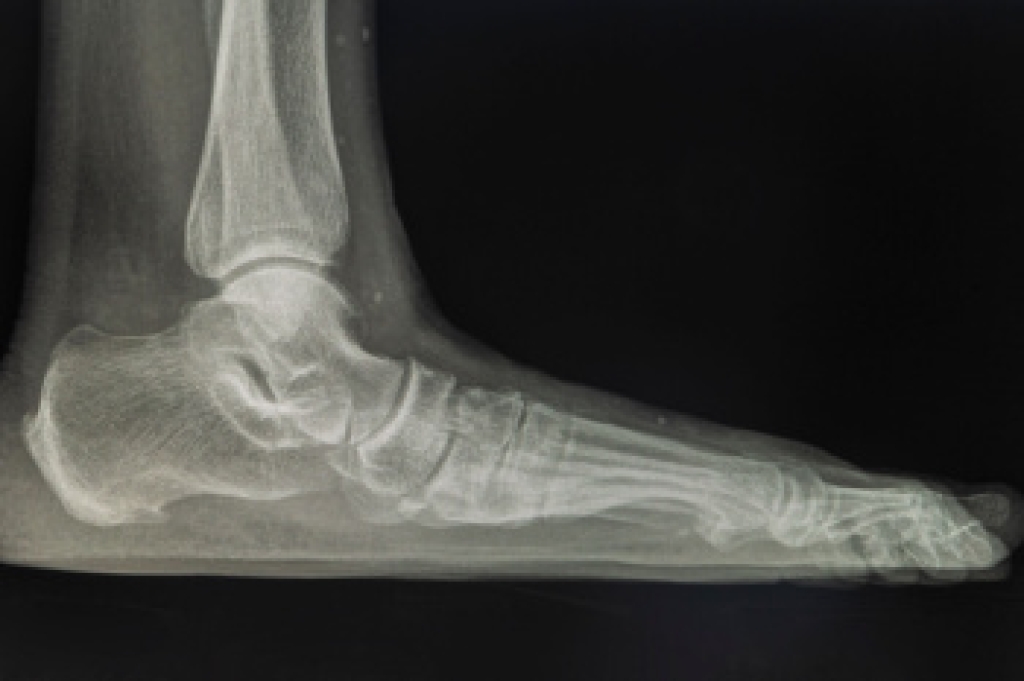

To figure out the cause of foot pain, podiatrists utilize several different methods. This can range from simple visual inspections and sensation tests to X-rays and MRI scans. Prior medical history, family medical history, and any recent physical traumatic events will all be taken into consideration for a proper diagnosis.

Diagnosis

Due to the wide variety of potential causes of ankle pain, podiatrists will utilize a number of different methods to properly diagnose ankle pain. This can include asking for personal and family medical histories and of any recent injuries. Further diagnosis may include sensation tests, a physical examination, and potentially x-rays or other imaging tests.